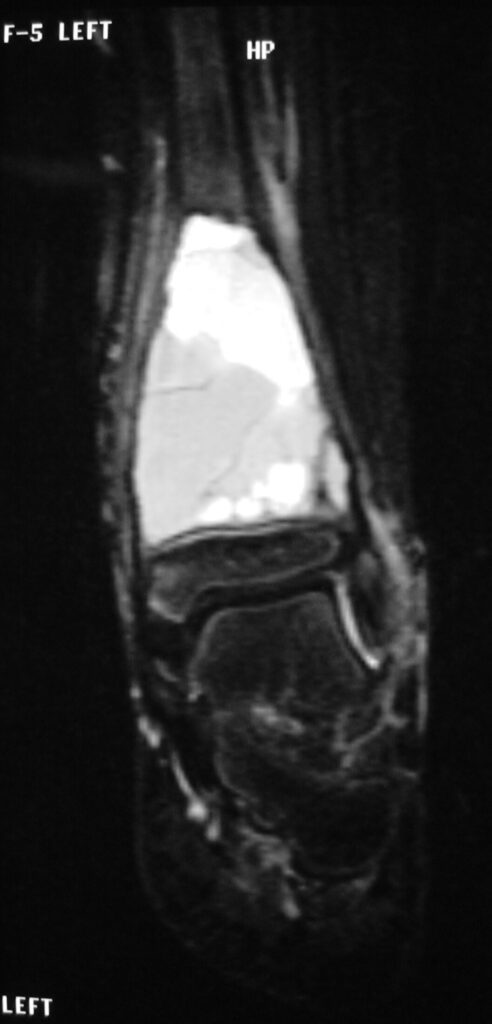

Fig 2 a-e. MRI of an ABC of Distal Tibia: Fig 2 a-c: geographic cystic expansile lesion with fluid-fluid levels. The fluid-fluid levels are caused by bleeding into the cavities. The blood collects and the degredation products settle to the gravity dependent areas of the cavities. This shows up as fluid-fluid levels on the MRI. Fig 2 d,e: This is a gadolinium enhanced MRI of the ABC of the distal tibia. There is peripheral and septal enhancement indication cyst formation. The contrast outlines the cystic cavities but does not enter into the center

Fig 2 a: Coronal T2 weighted MRI of an ABC

Fig 2c: Axial T2 weighted MRI of an ABC